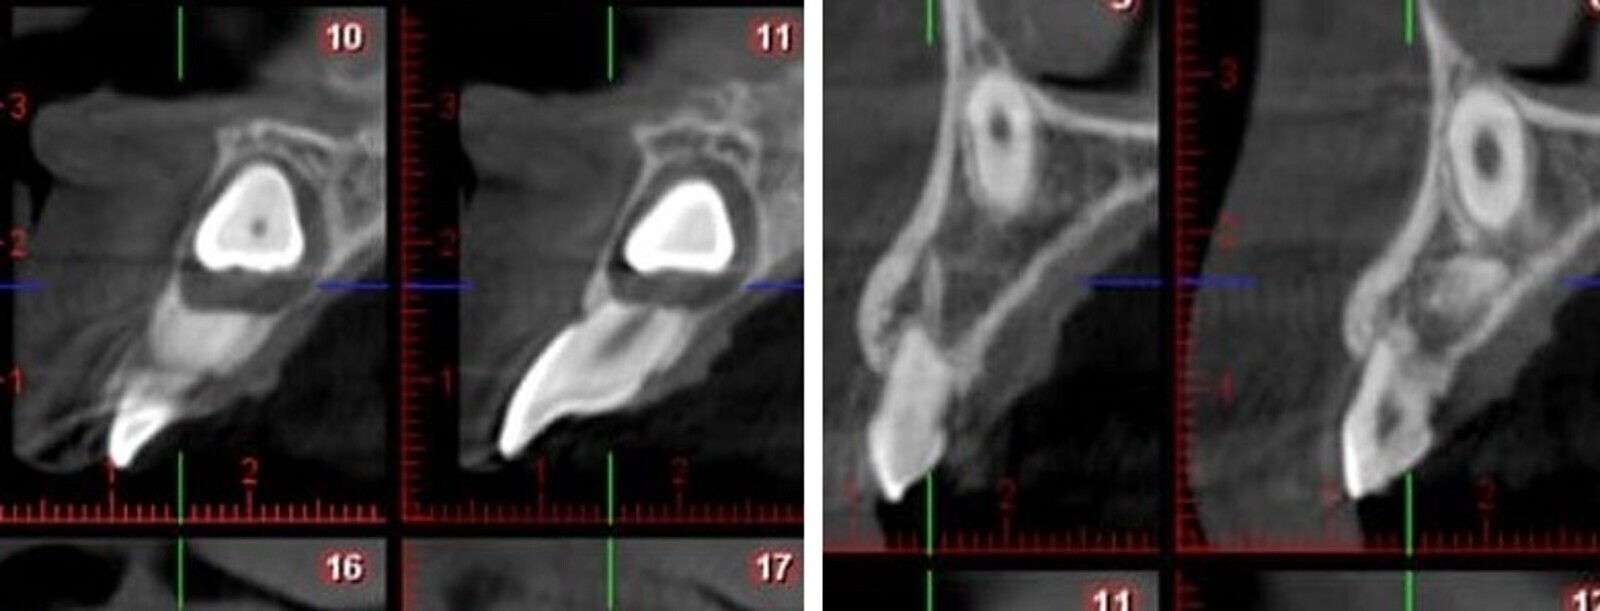

Fig. 2. Tomografía Cone Beam mostrando la reabsorción radicular de 11 y 53.

Fig. 3. Tomografía Cone Beam con las mediciones apropiadas.